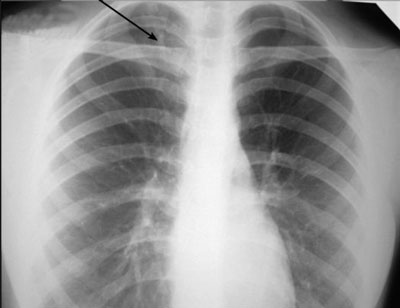

- Лучевая диагностика. Чтобы определить воспаление легких у взрослых, проводится такое обследование, как рентгеноскопия. Считается, что его результаты являются основополагающими в постановке диагноза, поскольку на снимке хорошо видно зону воспалительного процесса. Назначаться может и компьютерная томография легких.

Проведите рентгенологическое исследование легких, чтобы получить точное представление о состоянии легких и выявить возможное воспаление. Это поможет врачу поставить правильный диагноз и начать лечение.